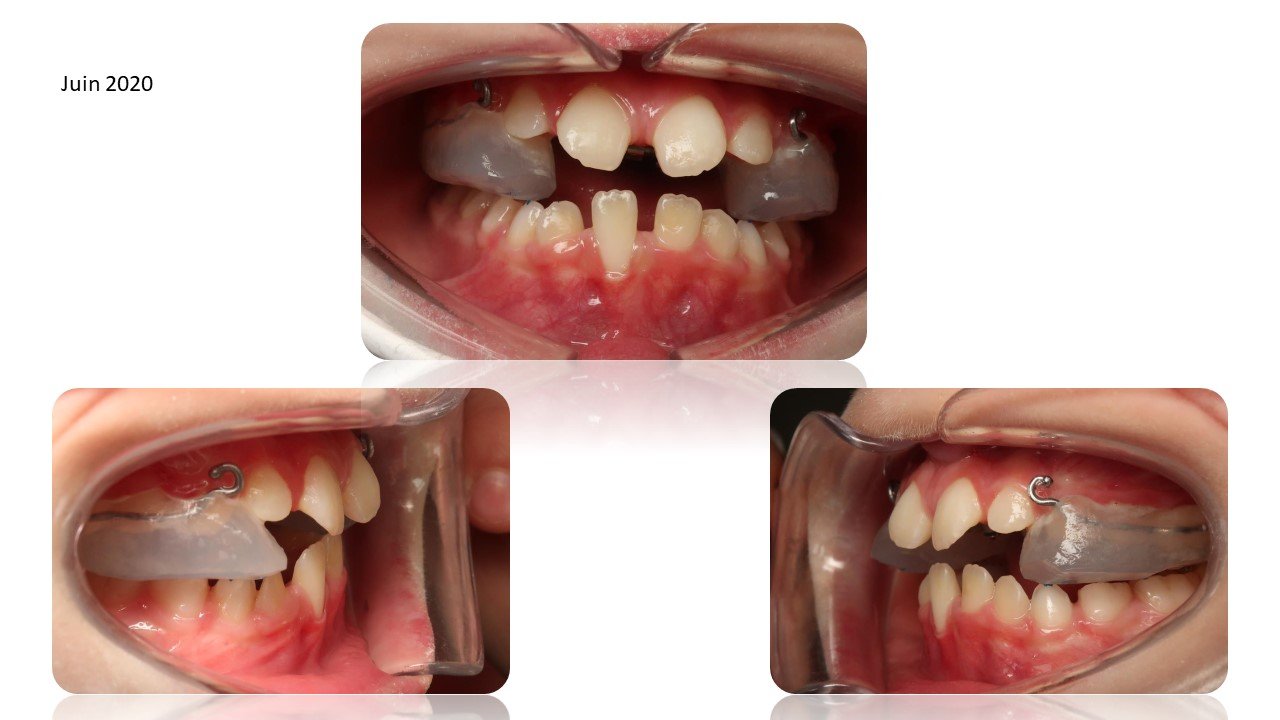

La Classe III Squelettiques

Les classes III squelettiques sont l’expression d’une orientation pathologique du plan occlusal et de la croissance faciale.

L’orthodontie systémique permet d’appréhender cette pathologie par l’analyse des latéralités mandibulaires.

Le traitement qui en découle est donc fonctionnel et stable car il permet non pas seulement une protraction du maxillaire mais une réorientation complète de celui-ci. Cette prise en charge permet de retrouver une proprioception maximale du prémaxillaire dans la mastication, gage de stabilité à long terme.